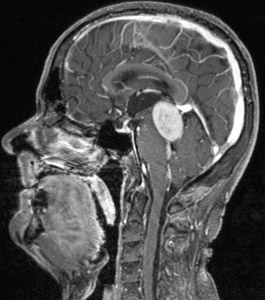

Μηνιγγίωμα οπισθίου βόθρου με πίεση επί του στελέχους

Άλλοι πιο σπάνιοι πρωτοπαθείς όγκοι του εγκεφάλου ειναι το μηνιγγίωμα, οι όγκοι υποφύσεως, τα νευρινώματα και οι όγκοι της επιφύσεως.

Οι υπόλοιποι πρωτοπαθείς όγκοι (μηνιγγιώματα, νευρινώματα ως επί το πλείστον) αφαιρούνται μικροχειρουργικά εάν ο όγκος βρίσκεται ανατομικά σε χειρουργικά προσπελάσιμο σημείο. Σε περίπτωση υπολειμματικού όγκου εφαρμόζεται η ακτινοχειρουργική με γ-knife ή Cyber-knife.